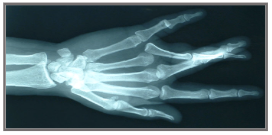

Radiographic film은 양쪽에 intensifying screen(증감지)가 놓이고, 균일하게 접촉되고 한 방향으로만 방사선적으로 투명하게 만든 raidographic cassette 의 핵심 요소임.

다음 그림은 film을 가운데 두고 양 쪽에 intensifying screen이 놓이도록 해주는 radiographic cassette(방사선 카세트)의 개략도임: